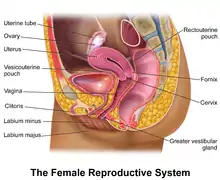

The female reproductive system is made up of the internal and external sex organs that function in the reproduction of new offspring. In humans, the female reproductive system is immature at birth and develops to maturity at puberty to be able to produce gametes, and to carry a fetus to full term. The internal sex organs are the vagina, uterus, fallopian tubes, and ovaries. The female reproductive tract includes the vagina, uterus, and fallopian tubes and is prone to infections.[1] The vagina allows for sexual intercourse and childbirth, and is connected to the uterus at the cervix. The uterus or womb accommodates the embryo which develops into the fetus. The uterus also produces secretions which help the transit of sperm to the fallopian tubes, where sperm fertilize ova (egg cells) produced by the ovaries. The external sex organs are also known as the genitals and these are the organs of the vulva including the labia, clitoris, and vaginal opening.[2]

The vulva is of all of the external parts and tissues and includes the following:[3]

- Clitoris: an organ located at the top of the vulva. It consists of the clitoral body and its pea-shaped glans that is protected by the clitoral hood. It also has two crus, two corpora cavernosa and two vestibular bulbs, which are erectile tissues that aid in clitoral erection as a part of sexual arousal by filling with blood.

- Labia: two types of vertical folds of skin called the labia majora (thick and large outer folds that protect other parts of the vulva) and the labia minora (thin and small inner folds that protect the vestibule from dryness, infections and irritation).

Vagina

Cervix

The cervix is the neck of the uterus, the lower, narrow portion where it joins with the upper part of the vagina. It is cylindrical or conical in shape and protrudes through the upper anterior vaginal wall. Approximately half its length is visible, the remainder lies above the vagina beyond view. The vagina has a thick layer outside and it is the opening where the fetus emerges during delivery.

Uterus

Fallopian tubes

Ovaries